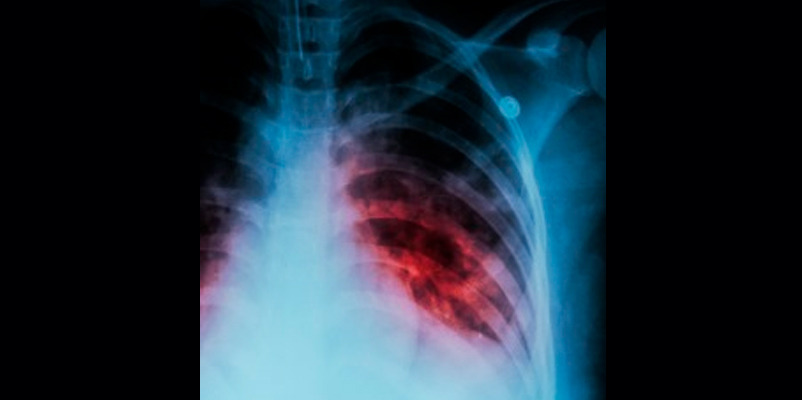

Las muertes por tuberculosis aumentaron el año pasado por primera vez en más de una década debido a la pandemia de la Covid-19, según el informe mundial sobre esta afección de la Organización Mundial de la Salud (OMS).

Los servicios de esta enfermedad, como muchos otros, fueron interrumpidos por la pandemia de la Covid-19 en 2020, pero el impacto resultó particularmente grave. Por ejemplo, aproximadamente 1,5 millones de personas murieron el año pasado por esa enfermedad, incluidas 214.000 personas con VIH.